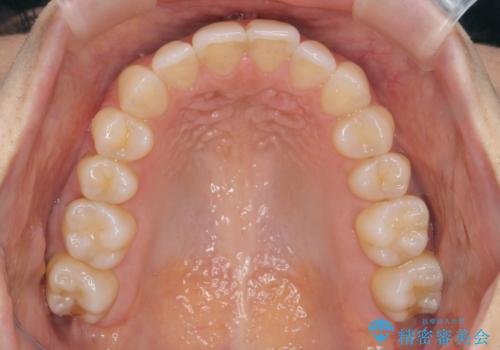

前歯のがたつきをしっかり治すマウスピース矯正

- 前歯のガタガタをきれいに並べたい、と希望され来院されました。

マウスピース矯正インビザラインのクリンチェックを用いて治療前にしっかりと歯並びのゴールのシミュレーションを行い、治療を開始します。

がたつきのないきれいな歯並びに仕上げることができ、満足いただくことができました。